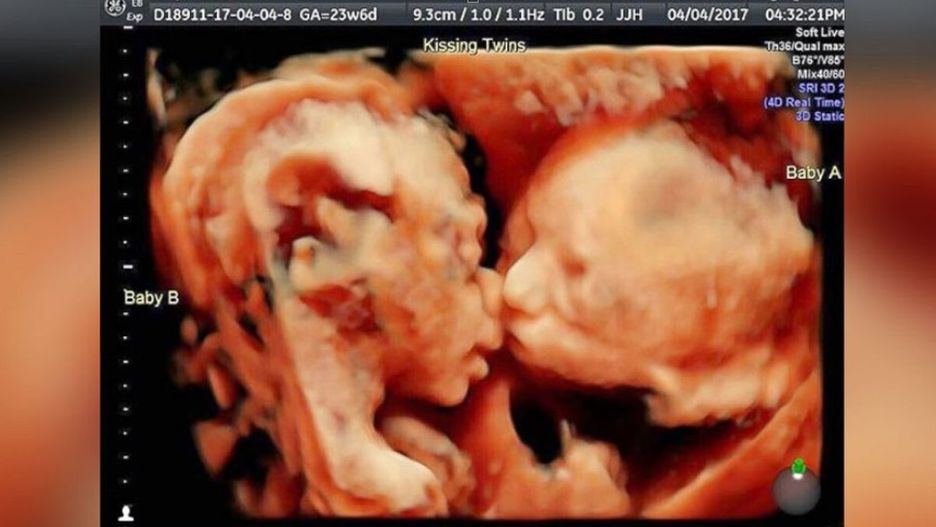

Badanie ultrasonograficzne to dla rodziców jedno z najważniejszych badań prenatalnych, ponieważ w łatwy sposób można podejrzeć rozwijający się płód, jego płeć oraz stan zdrowia. Ponadto wykonane w technologii 4D pozwala obserwować go w czasie rzeczywistym. W przypadku tych bliźniaczek stało się to dodatkowym atutem, ponieważ dziewczynki podczas badania postanowiły skraść sobie całusa.

Kiedy Carissa Gill była w 24. tygodniu ciąży postanowiła wykonać badanie USG 4D. Jest to USG trójwymiarowe w czasie rzeczywistym, co oznacza możliwość obserwacji dziecka, jego położenia w łonie matki i reakcji, w danym momencie.

W tym celu udała się do Fetal Vision Imaging w Pensylwanii (Stany Zjednoczone). Jednak nie spodziewała się, że wynik badania będzie tak zaskakujący. Bliźniaczki były bowiem ułożone w dość nietypowy sposób.

- Na tradycyjnym USG nigdy nie były tak blisko siebie, a tu leżały twarzą w twarz – mówi Gill. – Mogłam obserwować, jak ruszają ustami, jak się kopią nawzajem, ale to, co się stało na końcu, bardzo mnie wzruszyło. Bella pocałowała Callie w policzek – dodaje.

Carissa i Randy nie byli w stanie uwierzyć, w to co widzą. Również lekarz wykonujący badanie był w szoku. Pierwszy raz widział coś takiego. Niezwykłe badanie zostało zarejestrowane i szybko podbiło serca internautów.